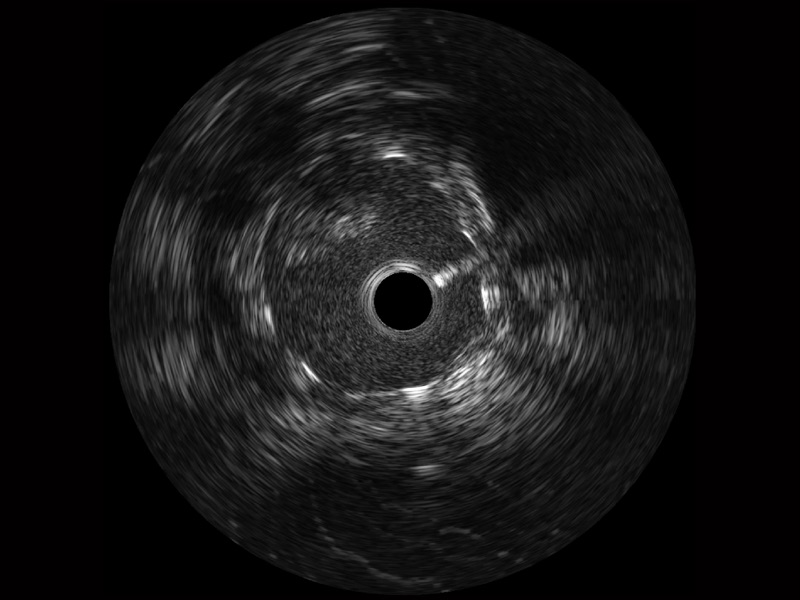

竞技宝(JJB)官方网站宽频IVUS图像

对比传统IVUS导管成像,竞技宝(JJB)官方网站宽频IVUS图像的近场支架梁显影更细腻,远场中膜外血管仍清晰可辨,兼顾远中近,兼顾分辨力与穿透深度